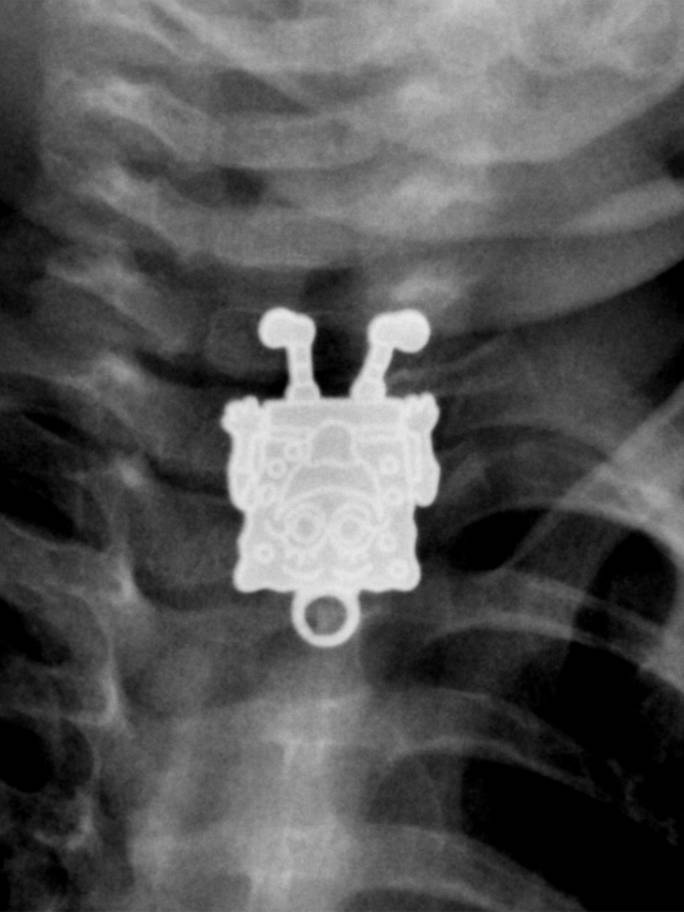

Humans are truly strange creatures and incredibly bizarre things can happen to us. These x-rays will shock even those who think they've seen it all.

X-ray it is one of the best inventions of mankind and in some situations it is indispensable. Especially because it often happens that people, especially children, they swallow objects that are not part of their daily diet. Not to mention the dogs who try to chew everything in sight and thus often end up swallowing inappropriate things.

Radiologists are already quite accustomed to seeing on X-rays strange things and some of these that we have collected for you in the gallery did not surprise them at all. Here is 15+ hacked and sometimes shocking x-rays.